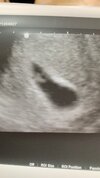

Kochane! Dziękuję pięknie za wszystkie kciuki i słowa otuchy! Nie mogę powstrzymać łez! Na szczęście, łez szczęścia... ❤️ Doktor jak tylko zasadził we mnie głowicę to od razu zobaczyłam moją fasolkę! Z serduchem jak dzwon.... doktor mówił ze tamten musial mieć zarówno słaby sprzęt jak i oko skoro nie widział nawet pęcherzyka żółtkowego.

Przedstawiam Wam mój mały cud ❤️